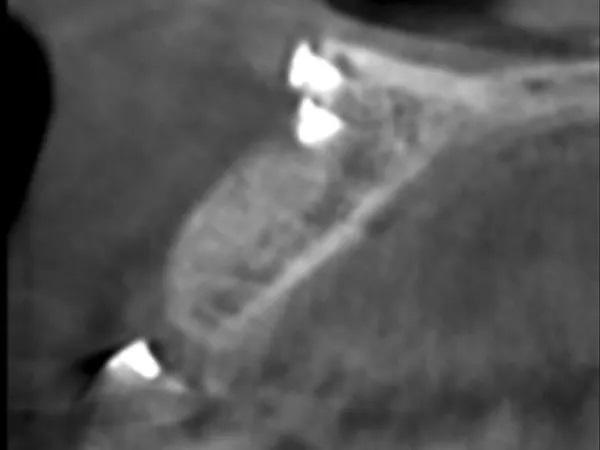

КЛКТ-снимок был выполнен перед повторным посещением через 6 месяцев, и на нем была видна достаточная высота и ширина кости для установки имплантата (Фото 16). При полном откидывании лоскута было обнаружено значительное увеличение ширины альвеолярного гребня в этом месте (Фото 17 и Фото 18). Установку имплантата (Straumann Bone Level Tapered Implant, 3,3 мм x 12 мм, Straumann) завершили, а индивидуальный формирователь десны затянули вручную, чтобы создать идеальный профиль выступания (Фото 19). На имплантат была установлена керамическая коронка с винтовой фиксацией через 4 месяца после установки имплантата (Фото 20).

Фото 16: На КЛКТ-снимке правого латерального резца верхней челюсти видна достаточная высота и ширина кости для установки имплантата.